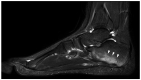

Autoinflammatory disorders are commonly characterized by seemingly unprovoked systemic inflammation mainly driven by cells and cytokines of the innate immune system. In many disorders on this spectrum, joint and bone involvement may be observed and imaging of these manifestations can provide essential diagnostic information. This review aimed to provide a comprehensive overview of the imaging characteristics for major diseases and disease groups on the autoinflammatory spectrum, including familial Mediterranean fever (FMF), Behçet disease (BD), crystal deposition diseases (including gout), adult-onset Still's disease (AoSD), and syndromatic synovitis, acne, pustulosis, hyperostosis, and osteitis (SAPHO)/chronic recurrent multifocal osteomyelitis (CRMO). Herein, we discuss common and distinguishing imaging characteristics, phenotypical overlaps with related diseases, and promising fields of future research.